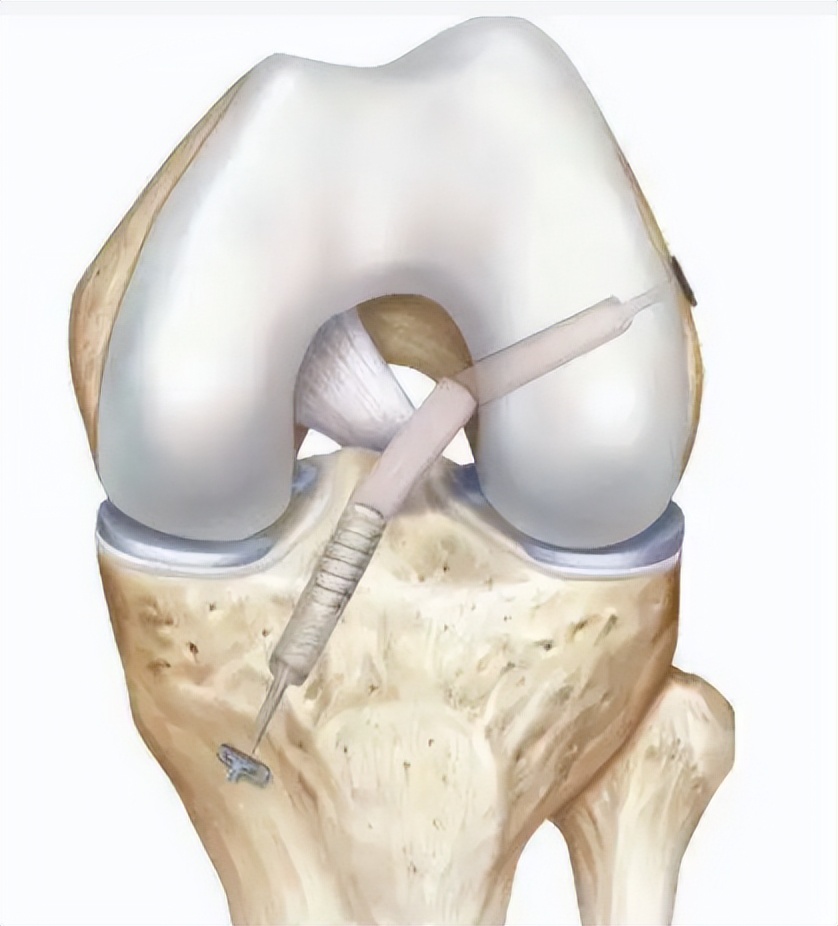

△前交叉韧带重建示意图

对于一度的损伤,可以选择佩戴支具进行保守治疗,而对于二度和三度损伤,已经出现膝关节的不稳定,则需要通过关节镜微创手术重建韧带,以恢复关节稳定性。

手术中,何河北医生采用微小切*技口**术,取出小张膝盖同侧的半腱肌,将肌腱编制后,再在关节镜下,于股骨以及胫骨建立骨隧道,使用可调节袢将肌腱悬吊在股骨隧道侧,最后用可吸收挤压钉将胫骨侧固定。